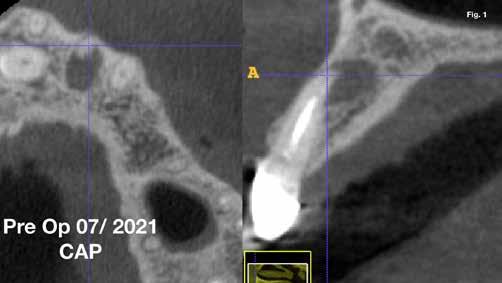

Anyagok és módszerek: 42 éves nő fordult a szerző rendelőjébe tüneti apikális parodontitisszel. A PA röntgenfelvételen az apex körül sugárzástól átlátszó kép és extrudált gyökércsatorna obturációs anyag volt látható, a CBCT-n megőrzött vestibuláris csont mellett (1–2. ábra). Mivel az elmúlt három évben kétszer

végeztek NSRCT-t, és a gyökércsatorna obturáció homogénnek, de túlságosan extrudáltnak tűnt, sebészi kezelés mellett döntöttek.